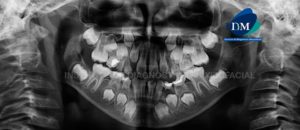

Paciente de sexo femenino de 45 años de edad acude al Instituto de Diagnóstico Maxilofacial para evaluación imagenológica integral. A la evaluación de la radiografía